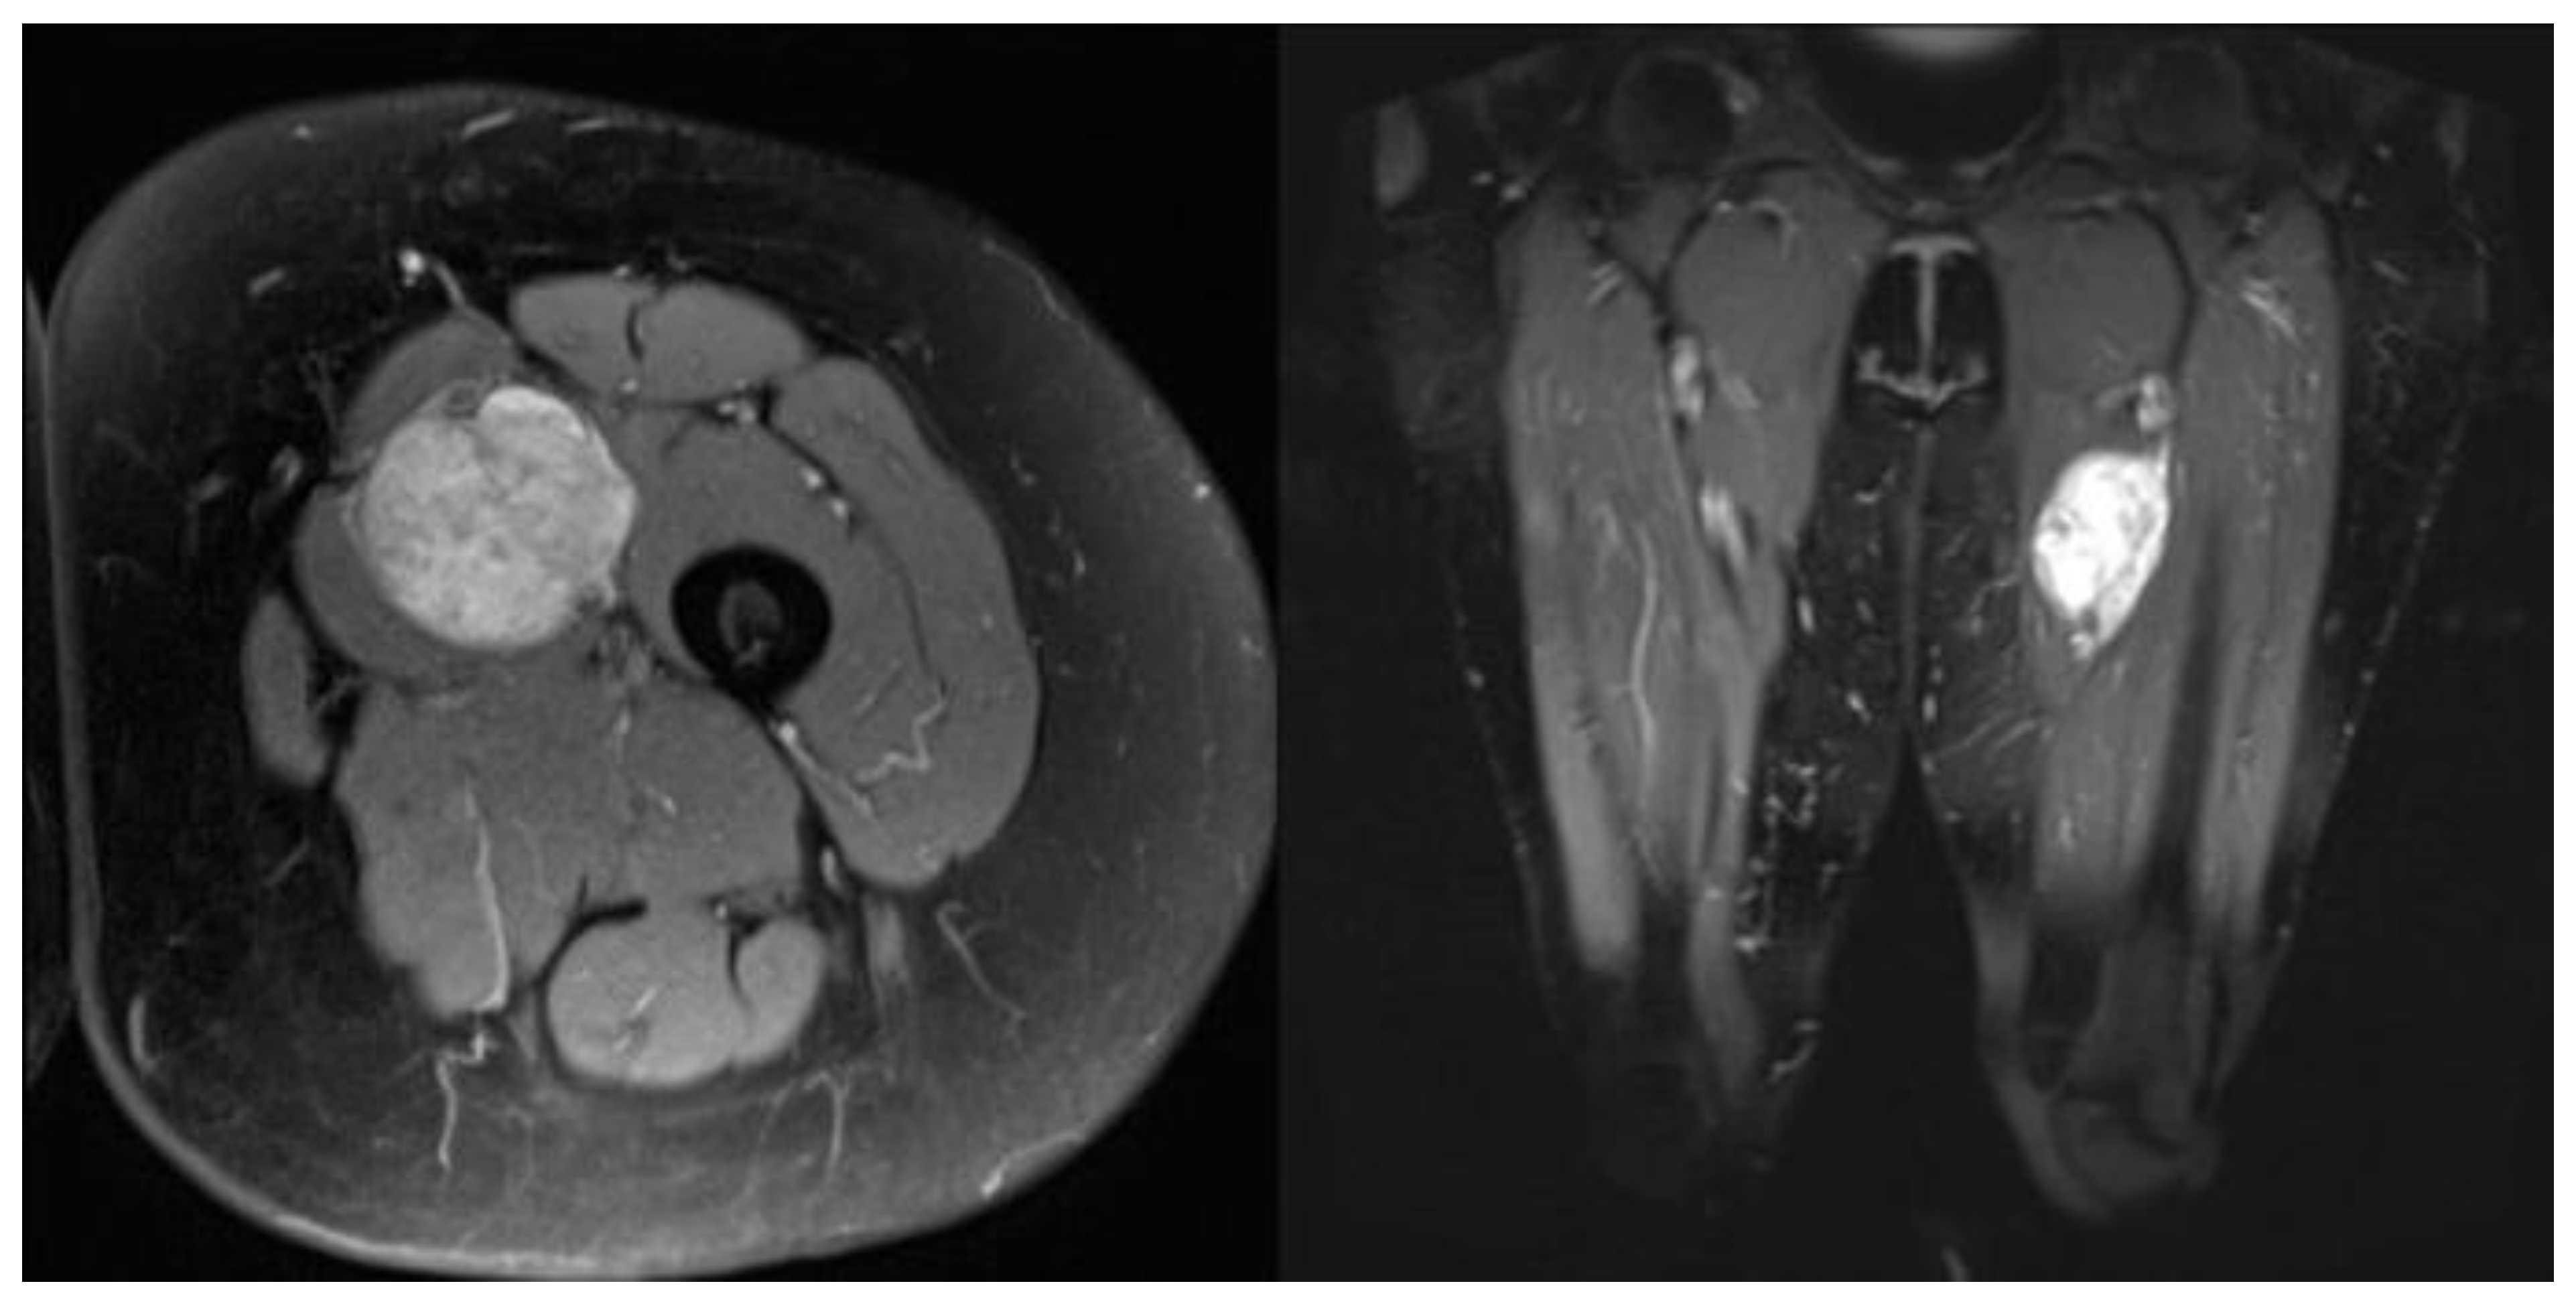

4. Results